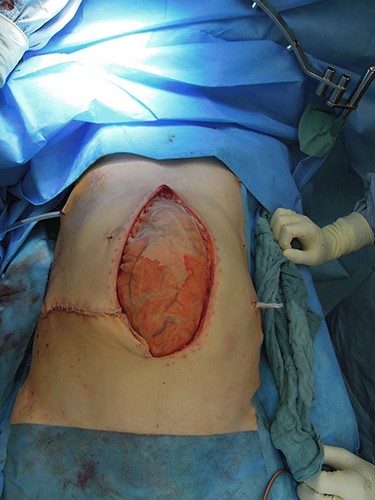

Revision laparotomy was performed, which showed a large diaphragmatic hernia on the right with intrathoracal right liver lobe, small bowel and colon (Fig. 5). The left-sided suture and mesh augmentation remained intact (Fig. 6). Due to the extended defect, only partial tension-free closure was possible, a Parietene composite® mesh was used (Figs 7 and 8) for bridging. Because of high intraabdominal pressure, primary abdominal wall closure was not possible; a gradual closure with an initially bridging vicryl mesh and vacuum therapy was performed (Fig. 9).